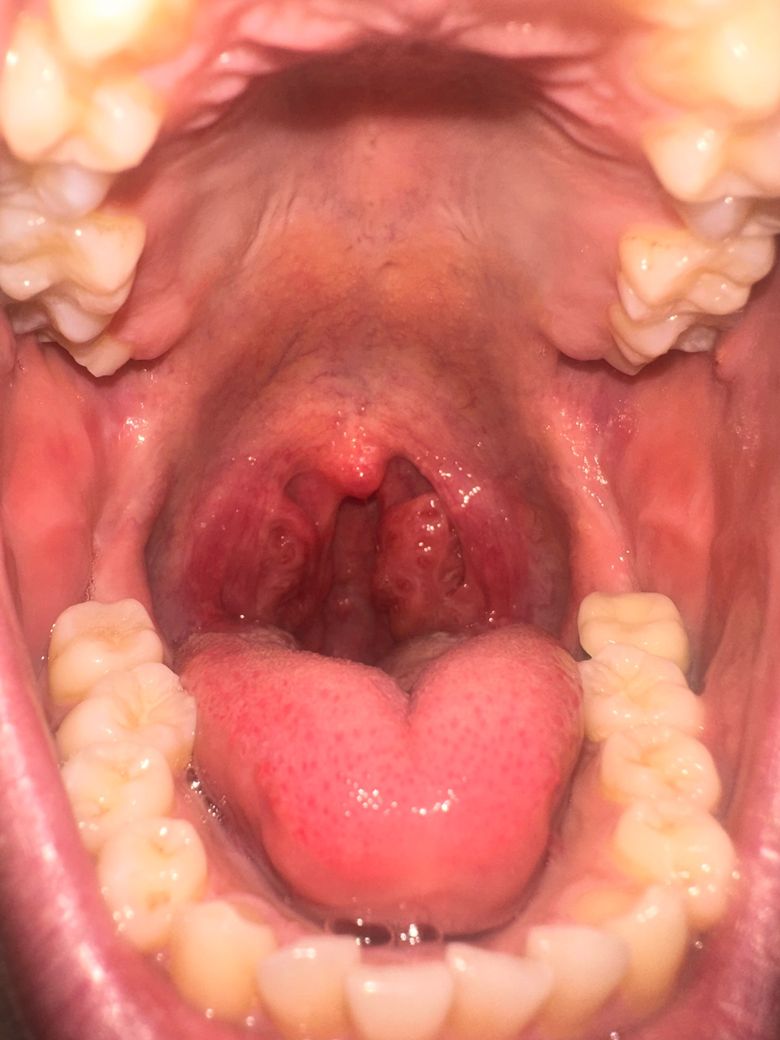

목에 이물감 느껴지는데 편도암일까요 ㅠ ?

원래 편도가 커서 편도염을 달고 살긴하는데 오른쪽 편도만 이물감 느껴지고 삼킬때 좀 아프네요 .. 증상은 3일정도 됐고 글을 쓰는 시점부터 항생제 먹었습니다 살짝 혹 같은게 있는거같기도 한데 근처 의원가니까 또 혹은 안보이고 염증만 있는거같다고 하시네여..

올려주신 사진에서 비대한 편도가 관찰되나 편도염 소견은 뚜렷하진 않습니다.

다만 인두부 점막의 염증이 의심되므로 물을 자주 마시고 과도한 목의 사용, 음주, 흡연, 카페인, 자극적이거나 지나치게 뜨거운 음식물의 섭취는 피하고 진통소염제 복용과 구강의 위생적 관리를 위해 가글을 권합니다.